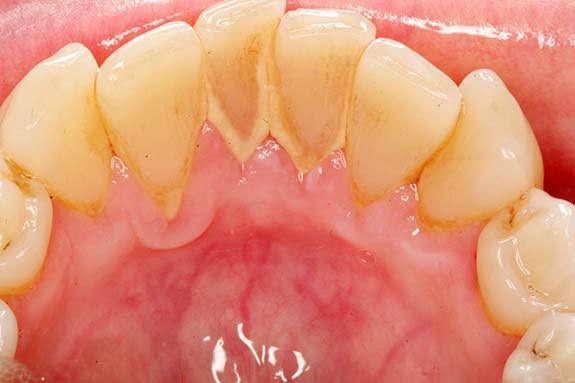

If you don’t brush and floss daily, plaque can harden into tartar. Only a dental professional can remove tartar. Extreme dental plaque and tartar can lead to: Cavities. Gingivitis and other forms of gum disease. Tooth infection (abscessed tooth). Tooth loss.